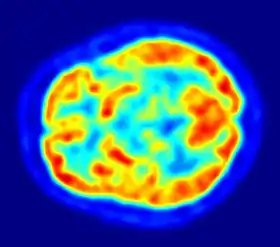

جهاز الرنين المغناطيسي الفعال (FMRI)

يستخدم هذا الجهاز في قياس التغيرات في الإشارات العصبية في الدماغ الناتجة عن تغيرات النشاط العصبي، وزيادة النشاط العصبي تؤدي إلى زيادة الاوكسجين الذي يتم استهلاكه، وبالتالي يعمل الجسم على زيادة نسبة الأوكسجين في الدم الأمر الذي يؤدي إلى زيادة نسبة الدم المشبع بالاوكسجين مقارنة مع الدم الغير مشبع بالأوكسجين. الدم المشبع بالأوكسجين والدم الغير مشبع بالأوكسجين يستجيبان بشكل مختلف للمجال المغناطيسي المتولد ومن خلال الاستجابتين المختلفتين يتم ملاحظة التغيير في النشاط العصبي.[6] أيضا يمكن رسم صورة ثلاثية الأبعاد للأوعية الدموية في النسج العصبية من خلال الاستجابتين المختلفتين لنوعي الدم.